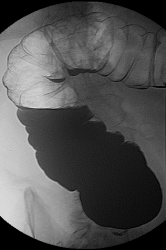

Виталий и Виктор здравствуйте! Есть еще три места вызывающие онкологическую настороженность - печеночный изгиб, нижняя стенка поперечно ободочной кишки недалеко от селезеночного изгиба и в нисходящей кишке по внутреннему контуру тоже близко от селезеночного изгиба - там вроде дополнительные образованя. Или показалось? Возможно так наслаивается позвоночник? + Искусственный сустав...

Здравствуйте Анатолий Владимирович, вообще мой учитель, отмечал настороженность на ректо-сигмоидный отдел прямой кишки, на углы(печеночный, селезеночный) и восходящий отдел ободочной кишки, об этом всегда помню и делаю снимки прицельные с предворительным вывидением на контуры, в продемонстрированном случае органической патологии прямой кишки и видимого дивертикулеза больше ни чего не визуализируется. Данный случай тоже не просто так выложил, малая форма очень редко встречается, обычно когда уже всё запущено или приличных размеров.